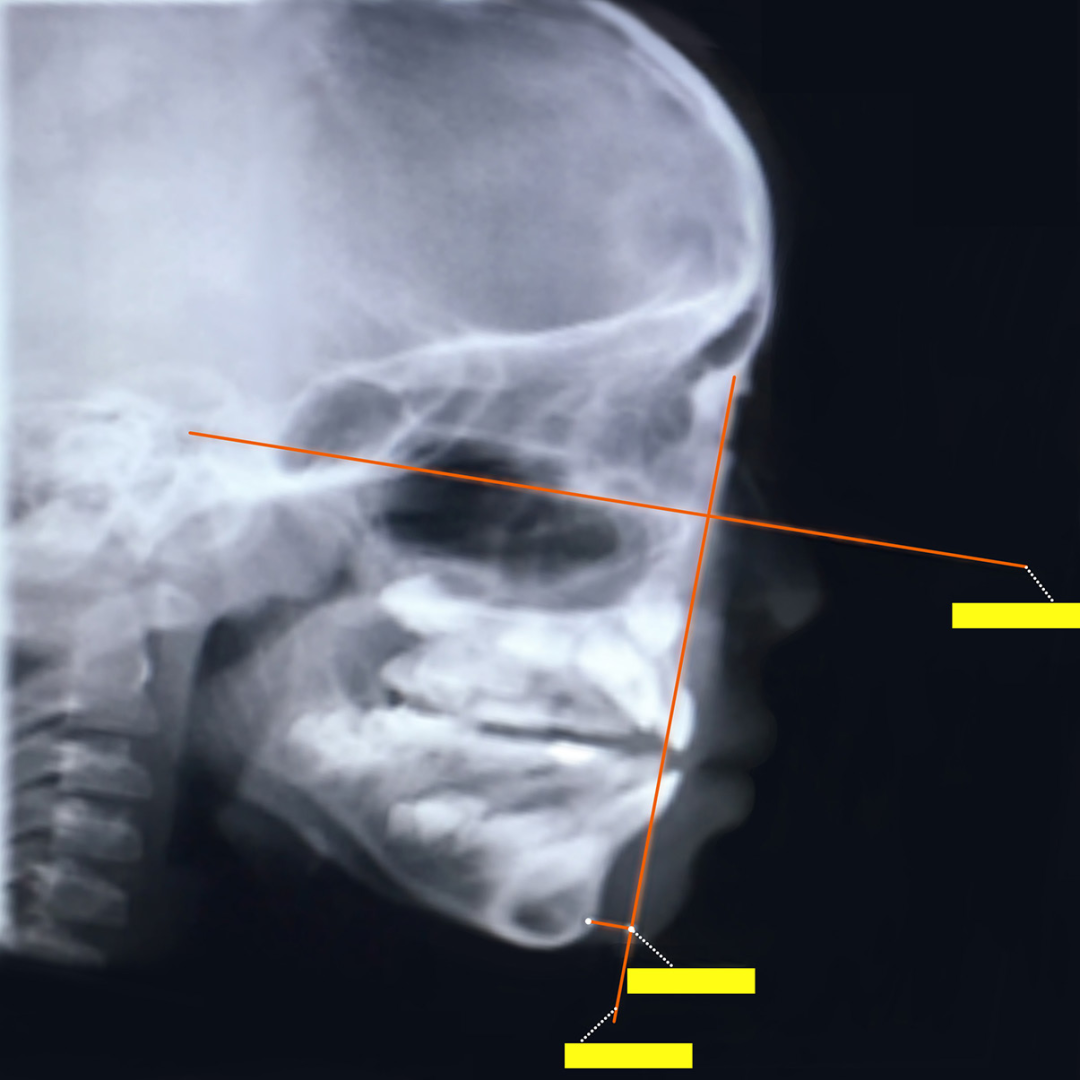

地包天面型一般是上前牙唇倾,下前牙明显舌倾。且大样本量的日本骨性地包天儿童人群研究显示,6~16岁之间,12~16 岁青少年的反地包天严重程度远远大于 5~11 岁的儿童。也就是说地包天下颌骨长度会随着年龄逐渐增加。

另外研究发现,地包天的髁状突并不是垂直向生长,而是向后生长,导致下颌前突,越向后生长,对下颌体长度影响越大。髁状突向后生长10mm,下颌体长度增加10mm,但是髁状突向前生长10mm,下颌体长度仅增加0.5mm。也就是说骨性地包天有高角的发育倾向。

就像这个小朋友初诊检查头侧片子发现骨骼I类、牙齿III类咬合关系。但是,孩子家长拒绝接受治疗,觉得孩子换完牙就变好了,不会变成严重的地包天问题。

但是1年半之后,孩子前牙地包天问题加重,下颌前凸也很明显,这才又想要通过牙齿矫正改善孩子的牙齿咬合和面型情况。